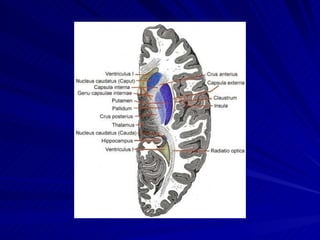

Parts of basal ganglia

The brain structures that comprise The Basal Ganglia  Putamen,  Caudate nucleus,  Globus pallidus  Substantia nigra  Subthalamic nucleus of Luys

The brain structuresthat comprise The Basal Ganglia Putamen, Caudate nucleus, Globus pallidus Substantia nigra Subthalamic nucleus of Luys